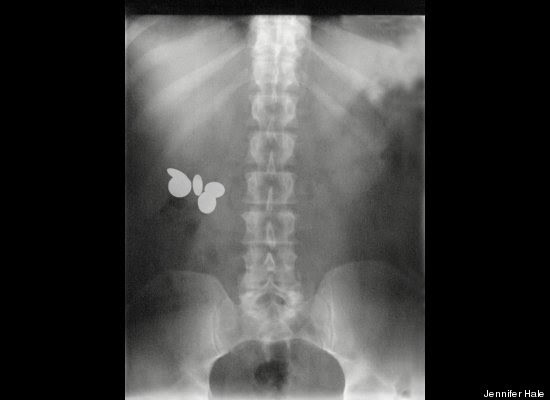

"Stack Up!" es una muy divertida colección de 100 imágenes de rayos X que muestra cuerpos extraños ingeridos o insertados en el cuerpo humano, tanto por accidente o de forma voluntaria, aunque se haga difícil imaginar el motivo de algunas de tales inserciones.

Los autores del libro -dos psiquiatras y un médico de sala de emergencias- aseguran -sin mucha originalidad pero con conocimiento de causa, que la imaginación humana no tiene límites. Esta afirmación es aplicable tanto a la calidad y variedad de objetos tragados o incorporados al cuerpo, como a los motivos o excusas utilizados para justificar la presencia de dichos objetos.

"Hay gente que hace cosas realmente imprudentes, y luego trata de racionalizarlas", advierten los autores en la solapa del libro, destacando precisamente la imaginación humana para "dar con usos imprevistos para objetos de la vida cotidiana".

"Tenía las manos ocupadas", "me caí encima", son algunas de las excusas que los profesionales de la salud escuchan de los pacientes que llegan a los hospitales con "cuerpos extraños extrañamente metidos en el cuerpo".

Redactado de manera humorística, el libro se pregunta cómo un teléfono celular puede haber ido a parar al sitio de la anatomía del propietario donde nunca da el sol, respondiéndose que, probablemente, estuviera en modo vibrador.

"Hallar un termómetro atascado en el recto de un adulto puede resultar corriente. Pero ¿Qué se puede decir de una muñeca Barbie, perteneciente a su hija de seis años?", se preguntan los autores, añadiendo el consejo infaltable: no hagan esto en casa.